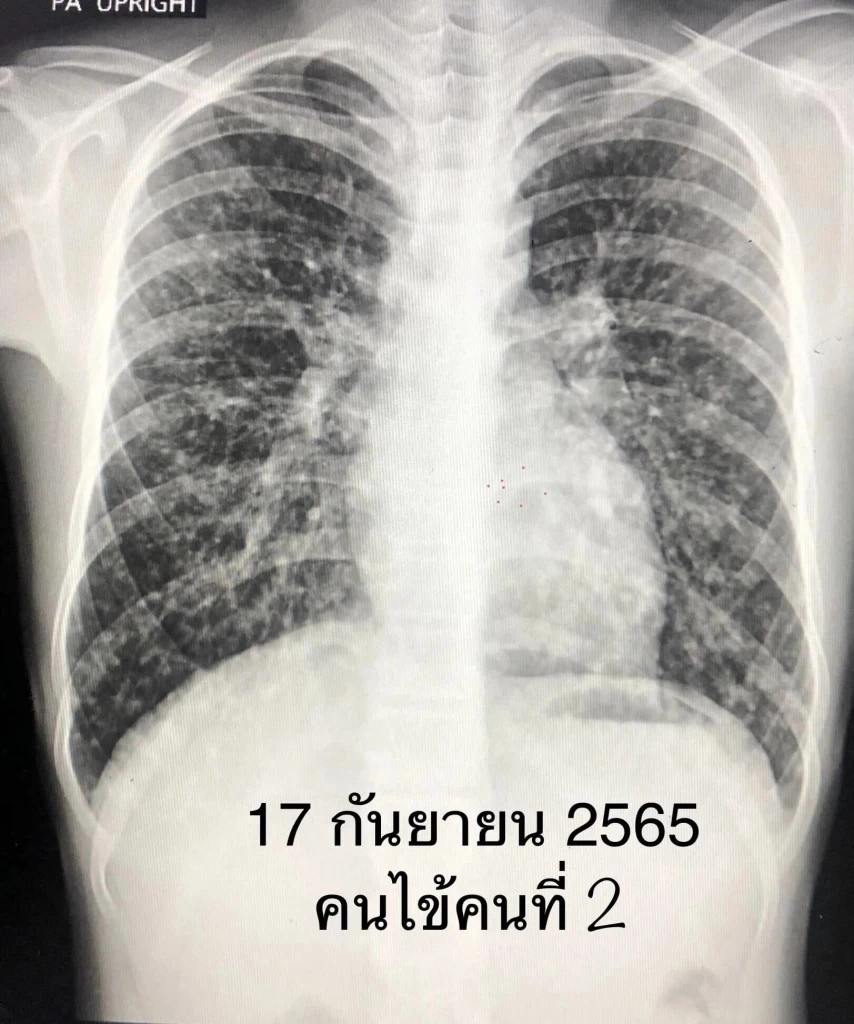

ผู้ป่วยหญิงอายุ 45 ปี ปกติแข็งแรงดี ไม่มีโรคประจำตัว วันที่ 30 กรกฎาคม 2565 ไปเที่ยวจังหวัดนครศรีธรรมราช เดินเข้าโพรงต้นไม้ใหญ่อยู่ห่างคลองวังหีบประมาณ 200 เมตร เพื่อไปดูค้างคาว ไม่ได้ใส่หน้ากากอนามัย อยู่ในโพรงต้นไม้ประมาณ 3 นาที หลังจากนั้น 15 วันเริ่มไอแห้งๆ บางครั้งไอมีเสมหะสีขาว อ่อนเพลีย ไม่มีแรง เดินขึ้นบันไดเหนื่อย เบื่อหาร น้ำหนักลด 2 กิโลกรัม ไม่มีไข้ ไม่ปวดหัว ไม่ปวดกระดูก ไปหาแพทย์วันที่ 5 ก.ย. 2565 เอกซเรย์ปอดผิดปกติ มีก้อนเล็กๆกระจายทั่วปอดทั้ง 2 ข้าง ทำคอมพิวเตอร์สแกนปอด และช่องท้อง พบก้อนเล็กๆในปอดกระจายทั่วปอดทั้งสองข้าง ก้อนในปอดด้านล่างขนาดใหญ่ถึง 1 เซนติเมตร (ดูรูป) พบก้อนในต่อมหมวกไตข้างซ้ายขนาด 0.5 x 1.1 เซนติเมตร และม้ามโตเล็กน้อย ได้ทำผ่าตัด ตัดชิ้นเนื้อจากปอดด้านซ้าย ส่งตรวจทางพยาธิวิทยา พบว่ามีเนื้อเยื่อตายและการอักเสบแบบแกรนูโลมา (necrotizing granulomatous inflammation) ไม่พบวัณโรค ย้อมสีพบเชื้อราลักษณะเป็นยีสต์ (ดูรูป) เพาะเชื้อราขึ้น Histoplasma capsulatum มีลักษณะเป็นราสาย (ดูรูป) Histoplasma อยู่ในกลุ่มรา 2 รูป (Dimorphic) อยู่ในเนื้อเยื่อมีรูปเป็นยีสต์ อยู่ในธรรมชาติมีรูปเป็นเส้นใยราสาย

สรุป: ผู้ป่วยเป็นโรคฮิสโตพลาสโมซิส จากการหายใจสปอร์ Histoplasma capsulatum หลังจากเข้าไปในโพรงต้นไม้เมื่อวันที่ 30 ก.ค. 2565 ทำให้เกิดปอดอักเสบ กระจายไปที่ต่อมหมวกไตและม้าม